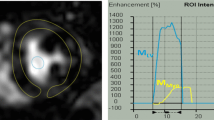

The FFRct analysis was carried out for the CCTAbase and the follow-up CCTA (CCTAfollow-up) for each patient by HeartFlow, Inc., using the same software version (FFRCT_3.14.0.7). The analysis provides all modelled focal anatomical stenoses of > 30% with their FFRct value measured 2 cm downstream of this stenosis (Fig. 2). FFRct values were measured at the most distal point in each of the three major coronary arteries (right coronary artery (RCA), LAD, and LCX). The length of the segmented part of the coronary artery sometimes varied between both analyses. Therefore, both FFRct analyses for each patient were placed side by side, ensuring that the measurement of the most distal point was at exactly the same location for both scans using the interactive viewer (Fig. 2).

Measurement of the number of focal stenoses and distal CT-derived fractional flow reserve values in a single patient at baseline and follow-up. The focal stenoses (indicated by HeartFlow, Inc.) and distal FFRct values were recorded from the FFRct analyses. A shows that the FFRctbase has no focal stenosis, whereas the same patient in B has one focal stenosis on the FFRctfollow-up with a value of 0.87 in the left circumflex artery. C displays the FFRctbase values at the most distal point of each of the three major coronary arteries, with the investigator placing the measurement pins. Since the length of the segmented coronary arteries varies between FFRctbase and FFRctfollow-up, the shortest segmentation available was used for the measurements. C The section distal to the 0.92 measurement point in the left anterior descending artery was disregarded. D shows the FFRctfollow-up values measured at the same location as in C, allowing for a direct comparison between the two analyses. Figure 1S illustrates the multiplanar and volume-rendered images of the distal left circumflex artery stenosis at baseline and follow-up, corresponding to the patient in Fig. 2. FFRct, CT-derived fractional flow reserve